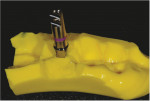

In the patient's mouth, the stock healing cap was removed from the implant, an impression post (RC Impression Post, Straumann) was inserted and hand tightened, and an impression was made with the impression material. The impression post was then unscrewed from the implant, screwed into an implant analog (RC Bone Level Implant Analog, Straumann), and replaced into the set impression (Figure 10). Next, this impression was placed onto the cast such that the implant analog and impression post fit into the void left after the tooth fragments were removed (Figure 11 and Figure 12). Orthodontic wax was then used to seal the gap between the analog and the cast to the level of the analog head (Figure 13). With the wax in place, the base of the cast was soaked in water, and then a second base was poured onto the cast to embed the implant analog. The impression was removed from the cast, and the impression post was unscrewed from the analog (Figure 14).

After ensuring that the wax was smooth to the top of the implant analog head, a temporary abutment (RC Temporary Abutment, Straumann) was air abraded and screwed into the analog. A bis-acryl composite resin (3M™ Protemp™, 3M Oral Care) was then injected around the abutment to the level of the gingival margin (Figure 15). Once polymerized, the abutment was removed from the cast, and it was observed that the resin flowed completely to the base (Figure 16). The transition between the base of the abutment and the gingival margin was then smoothed (Figure 17). To complete the custom healing abutment, the subgingival portion of the restoration was polished, and the protruding abutment was cut off and made smooth with the top surface (Figure 18). When compared with a stock healing cap, a custom healing abutment fabricated with this technique will look wide and flat.